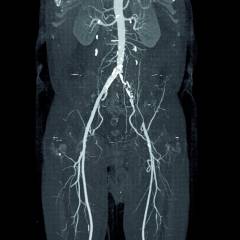

Ангиография сосудов конечностей

Ангиография сосудов конечностей — это диагностика артерий и вен верхних и нижних конечностей.

Где вводится контрастное вещество? Для исследования верхних конечностей 10-15 мл контрастного вещества вводят в плечевую артерию. Для нижних конечностей катетер помещается в бедренную артерию или брюшную аорту. При необходимости контрастирования сосудов голени и стопы выполняется пункция задней большеберцовой артерии.

Как осуществляется рентгенография? После заполнения сосудов контрастом проводят серийную рентгенографию с использованием двух рентгеновских трубок, расположенных перпендикулярно друг к другу, которые включаются одновременно с определенными интервалами.

Какие ощущения могут возникнуть во время процедуры? Благодаря местной анестезии введение катетера безболезненно. При введении контрастного вещества может возникнуть ощущение жара и металлический привкус во рту.